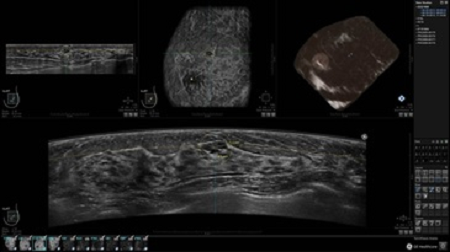

• Получение объемных 3D изображений с возможностью покадрового просмотра

• Отображение объемных 3D ультразвуковых изображений, которые состоят из традиционных поперечных и воссозданных коронарных и сагиттальных проекций

• Возможность отображения полного 3D изображения

• Многооконный просмотр: 4 - 12 изображений

• Стандартизованная ориентация изображения: «толстый срез» в коронарной плоскости; поперечная; сагиттальная плоскость; радиальный и антирадиальный поворот изображения; просмотр исключительно области интереса

• 360 ° APC - отображение области по «любой точке компаса»